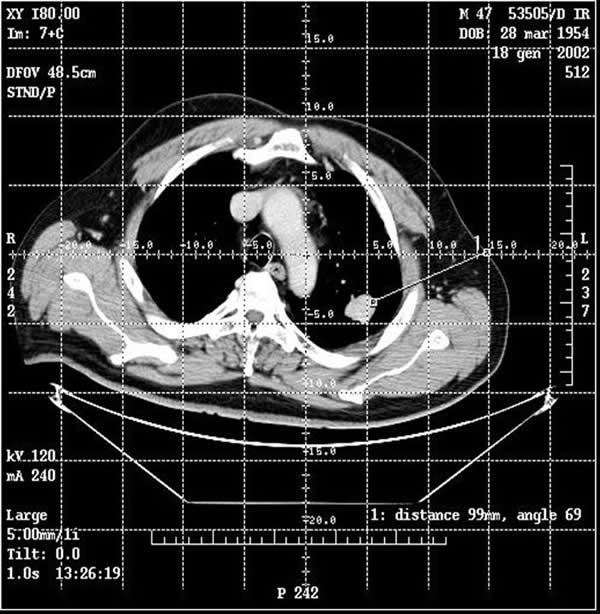

The procedure is performed with the patients under conscious sedation (Ketorolac 0.5-0.8 mg/kg, propofol 1-2 mg/kg/h, and remifentanil 0.1mg/kg/min) and local anesthesia (subcutaneous 1% xylocaine). Vital signs are continuously non-invasively monitored. CT guidance is employed in most of the cases; it is usually enhanced by the administration of contrast material before and after coagulation to obtain information about the real effectiveness of the procedure (Figure 3). In a selected group of patients with the tumour in contact with the thoracic wall, it is possible to work under ultrasound guidance (Video 2). The needle-electrode is inserted through an intercostal space after administration of local anaesthesia (Video 3). The correct placement is confirmed by CT (Figure 4) or ultrasound (Video 4) before applying the radiofrequency energy. The target temperature of ablation is 90°C. It is maintained for a time ranging from 15 to 27 minutes according to the size of the tumor; this variable also determines the gradual deployment of the electrodes, starting from 2 cm and then 1 cm for each step. When technically feasible, the ablation zone should include the whole lesion and one cm of the surrounding lung parenchyma.

Figure 4. A CT scan confirmed the correct placement of the needle with the deployment of the electrodes into the tumor.